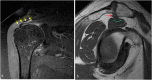

The rotator cuff is a group of four muscles and tendons surrounding the shoulder joint providing it strength and stability. The rotator cuff consists of the subscapularis, supraspinatus, infraspinatus and teres minor. Many shoulder complaints are caused by rotator cuff pathology such as impingement syndrome, tendon tears and other diseases e.g. calcific tendonitis. Diagnosis starts with clinical history and physical examination, after which imaging is often used to help confirm clinical findings depending on the differential diagnosis. The aim of the article is to review the frequently used imaging modalities to assess the rotator cuff and cuff-related disease, specifically focusing on radiography, ultrasonography and magnetic resonance imaging. This article will outline the advantages and disadvantages for each modality and illustrate typical radiological findings of common rotator cuff pathologies.